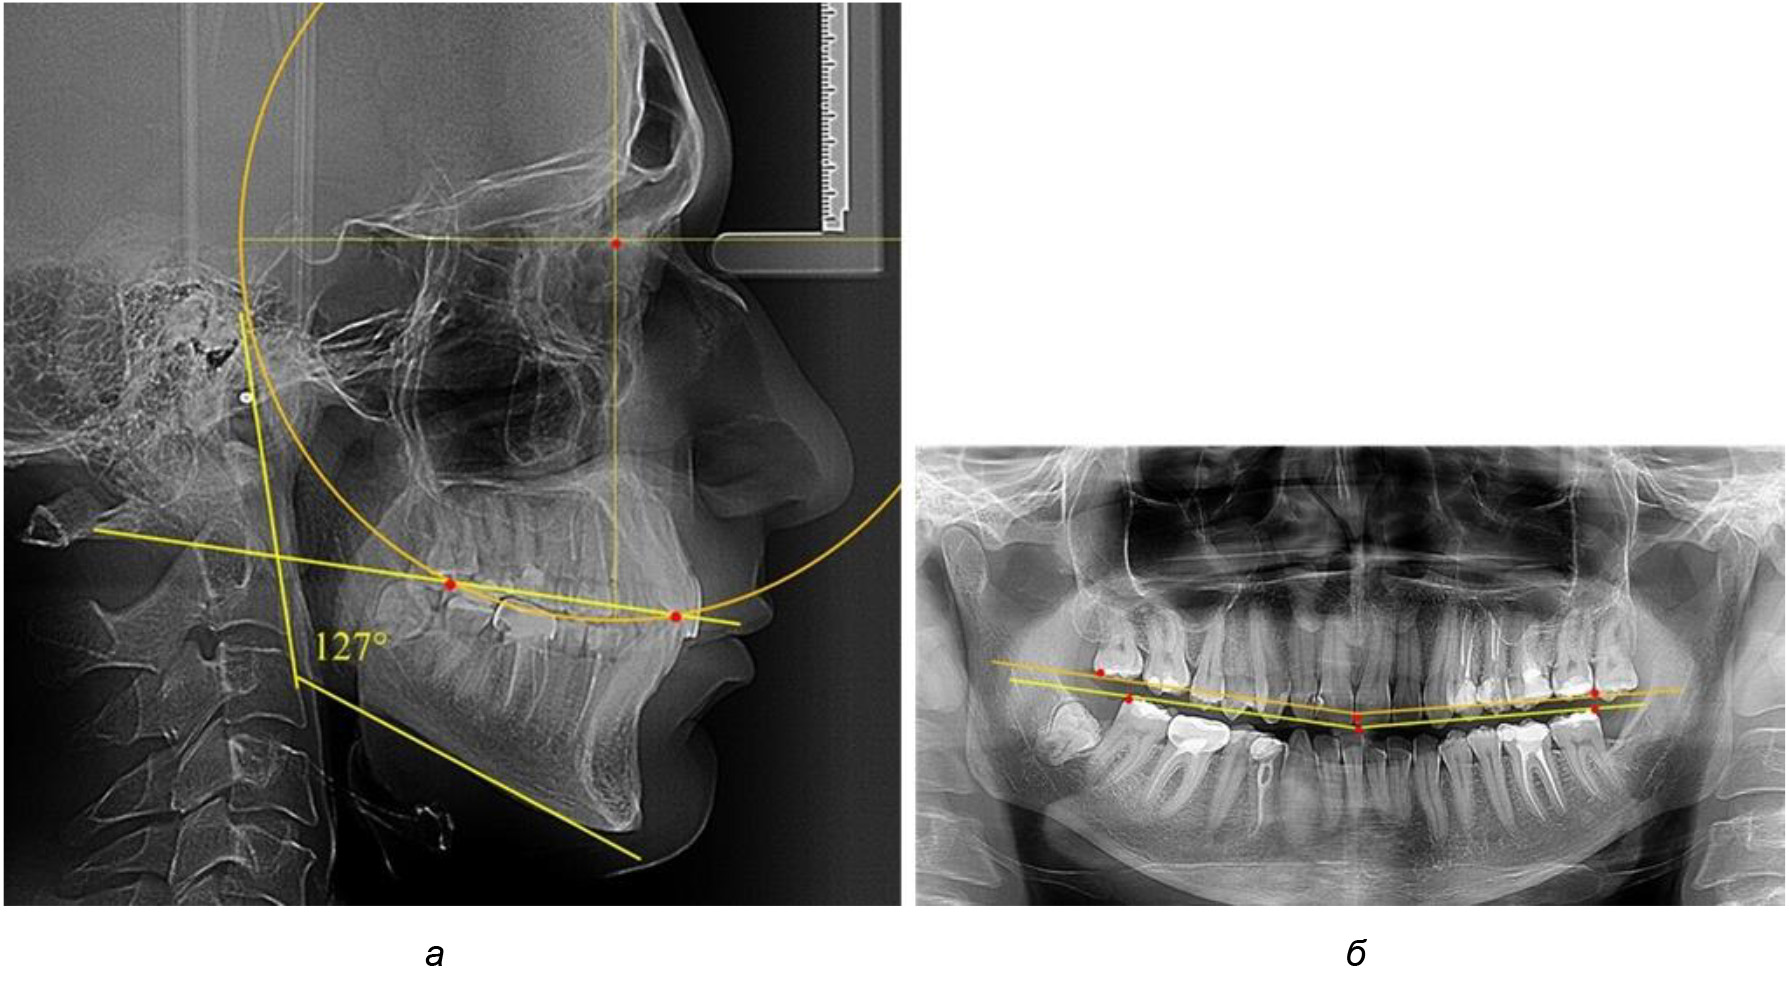

В ходе исследования установлено, что в 1-й подгруппу вошли ТРГ и ОПТГ 18 человек 1-й группы, что составило (29,03 ± 5,78) % от всех пациентов, рентгенограммы которых были проанализированы. У всех пациентов величина угла нижней челюсти была более 125° и в среднем составила (129,89 ± 3,62)° и характеризовала вертикальный тип нижней челюсти.

Деление величины радиуса круга к длине окклюзионной линии составило 1,623 ± 0,02. Таким образом, для определения радиуса окружности, соответствующей кривизне окклюзионного контура боковой ТРГ, необходимо измерить расстояние между передней и задней окклюзионными точками и последующим умножением полученной величины на число Фибоначчи (рис. 2).

Рис. 2. Особенности кривой Spee на ТРГ (а) и ОПТГ (б) у людей с признаками вертикального роста

После лечения пациентов техникой «прямой» дуги, так же как и в 1-й подгруппе, было отмечено увеличение сагиттального размера окклюзионной лини в среднем на (2,38 ± 0,83) мм. Окклюзионная линия практически касалась окклюзионного контура всех жевательных зубов, и отмечалось практически полное отсутствие кривой Spee, так же как и у людей 1-й подгруппы 2-й группы (рис. 6).

Рис. 6. Особенности ТРГ при оптимальной кривой Spee до лечения (а) и после лечения (б) техникой «прямой» дуги

Таким образом, проведенное лечение техникой «прямой» дуги способствует нормализации окклюзионного равновесия и торку передних зубов, однако не соответствует оптимальному окклюзионному статусу, характеризующему физиологическую окклюзию. При этом величина нижнечелюстного угла оставалась на прежнем уровне.